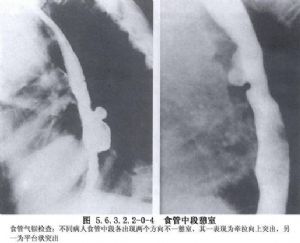

食管中段憩室的诊断主要依靠食管钡餐造影检查和内镜检查。在做钡餐造影检查时,患者取头低脚高位或俯卧位,或取左侧卧位,憩室的位置和轮廓容易显示。必要时做食管CT检查和食管功能测定,以除外其他较严重的疾病。如果出现慢性肺化脓症的症状,则有必要做气管镜检查和肺CT扫描,以明确肺部病变的范围。如怀疑有憩室-支气管瘘,须做支气管碘油造影或气管镜检查;内镜检查有助于发现瘘口。嘱患者口服亚甲蓝或其他染料,若在痰中发现蓝色,即可以确诊(图5.6.3.2.2-0-1~5.6.3.2.2-0-4)。